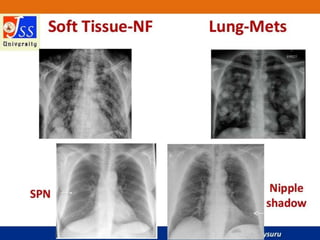

Chest X-rays are commonly used medical imaging tests that produce images of the structures and organs inside the chest such as the heart, lungs, blood vessels, and soft tissues. They can be used to diagnose conditions like pneumonia, lung cancer, and heart failure by detecting abnormalities in these structures. Chest X-rays expose patients to a very small dose of ionizing radiation but provide valuable medical information to guide diagnosis and treatment.